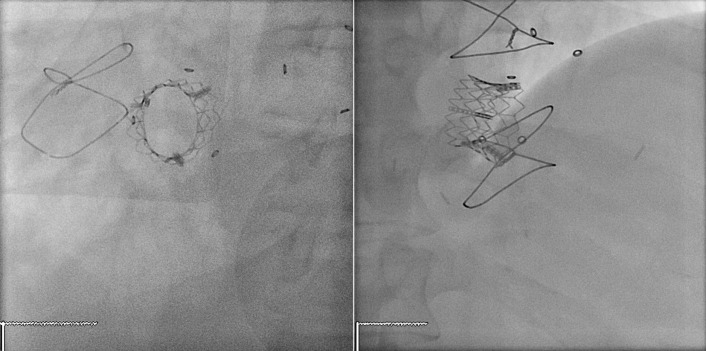

Transcatheter/percutaneously inserted heart valves are increasingly implanted. Most commonly, they are inserted into the pulmonic position or right heart conduits in the previously repaired congenital heart disease population ( Figs. 13-1 and 13-2 ) and into the aortic position ( Table 13-1 ; Graphics 13-1 and 13-2 ; Figs. 13-3 to 13-10 ), but they can also be placed into atrioventricular valve positions and into bioprostheses or conduits in any position.

Percutaneous valves are generally supported by radiographically obvious stents, the design of which allows for initial contraction of the prosthesis onto a catheter and release/self-expansion from the catheter.

Percutaneous/transcatheter heart valves are constructed of either bovine jugular venous valves that are suspended on wire mesh cages (Bonhoeffer design/Melody Transcatheter Pulmonary Valve–TPV, Medtronic), or consist of a valve created from bovine pericardial tissue that is suspended on wire mesh cages (Edwards Sapien and Medtronic CoreValve). Percutaneous aortic valve implantation is currently one of the most rapidly proliferating percutaneous interventions in the world ( Figs. 13-11 to 13-13 ).